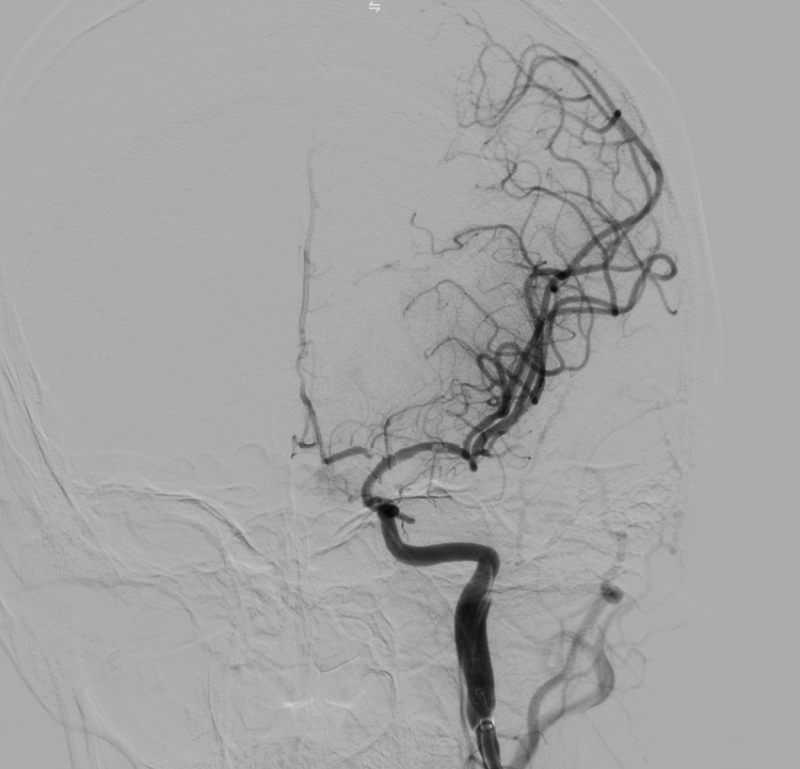

Hình ảnh: DSA sau can thiệp tái thông TICI 3

Kíp can thiệp do Th.bác sĩ Giáp Hùng Mạnh, Trưởng khoa Thần kinh VLTL-PHCN, Bệnh viện Bãi Cháy cùng ê kíp thực hiện. Sau can thiệp, tình trạng người bệnh ổn định, tỉnh táo hơn, cải thiện vận động, sức cơ chân phải đạt 3/5, huyết áp 110/70 mmHg và đang tiếp tục được theo dõi, điều trị tại bệnh viện.